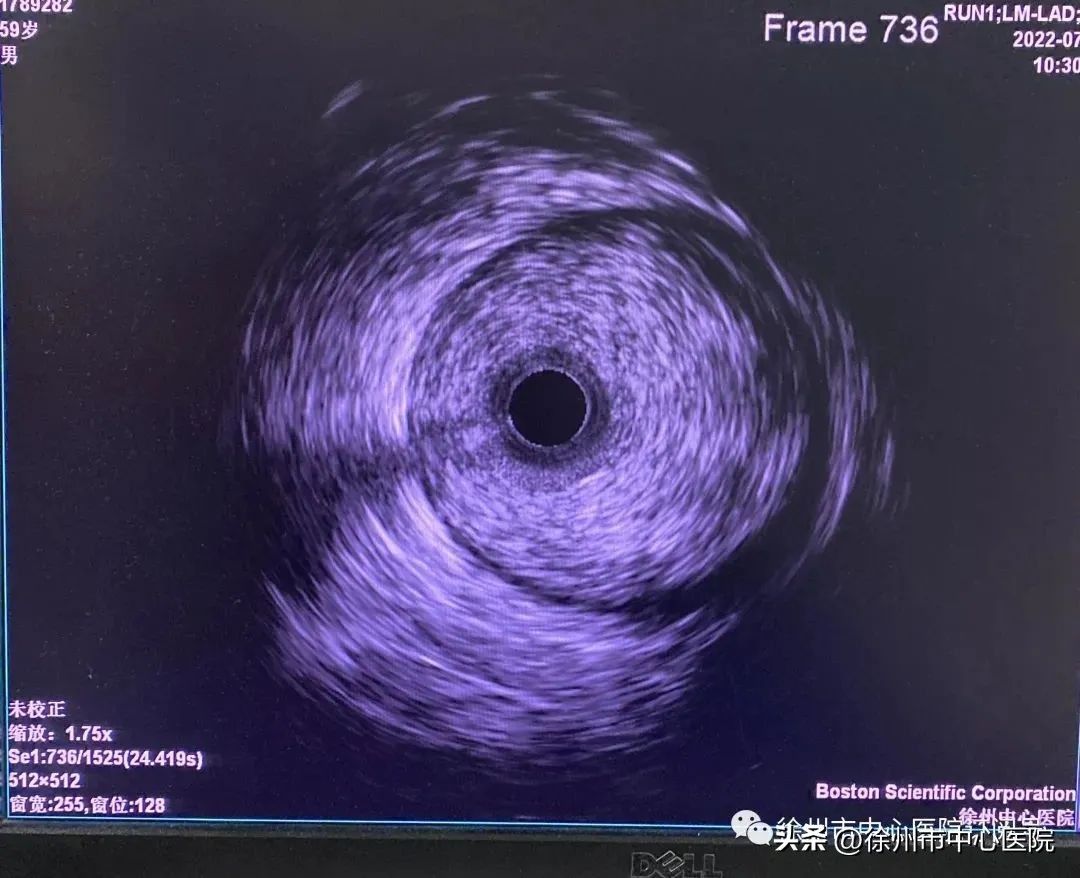

血管内超声影像图

据李明哲介绍,血管内超声(IVUS)是近年来兴起的先进诊断方法,通过导管技术将 头发丝般细小 的微型超声探头送入 血管腔内进行360°扫描 ,显示血管横截面图像,从而提供在体血管腔内的清晰影像。

血管内超声也被称作冠状动脉的“第三只眼”,能够将冠脉血管内病变“看”得更加仔细,从而精确测定管腔、血管直径以及判断病变严重程度及性质,在辅助诊断冠状动脉粥样硬化、冠心病介入治疗中均具有明显优势,进一步提高了诊断的精确性、科学性,避免了经验性支架植入,对冠脉介入治疗策略、支架选择和效果评价有着重要的指导意义。

血管内超声(IVUS)是指无创性的超声技术和有创性的导管技术相结合,使用末端连接有超声探针的特殊导管进行的医学成像技术。它通过心脏导管将微型化的超声换能器置入心血管腔内,显示心血管断面形态和血流图形。

1、小身材 , 与传统的医用超声探头相比,血管内超声探头最显著的特点是个头小,只有1.2毫米-3毫米。微型超声探头由相控阵型环状排列的多晶体换能器所组成,能够生成360度血管截面图像,并且探头轮廓光滑,易于插入,血管损伤可能性也很小。